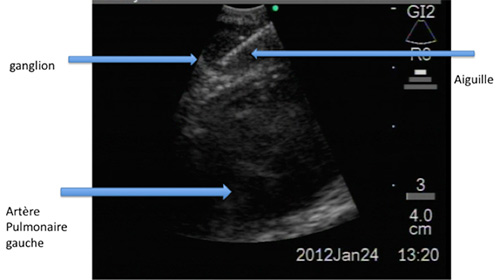

Ces ponctions peuvent être réalisées grâce au

guidage du scanner ou sous échographie endo-bronchique (photo 1). Le ganglion

fait ici mois de 10 mm de diamètre . il est au contact de l'artère pulmonaire

et pourtant il peut être ponctionné en toute sécurité grâce au guidage

échographique de l’écho-endoscope.